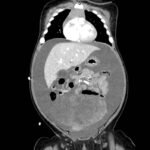

A 5-month-old female presented to the emergency department with worsening abdominal distention and postprandial emesis. Point-of-care ultrasound (POCUS) demonstrated extensive abdominal free fluid with a large, heterogeneous mass in the suprapubic region. This was confirmed on computed tomography (CT) of the abdomen and pelvis. The patient was urgently taken to the operating room for exploratory laparotomy where a ruptured tumor was discovered. The patient was eventually diagnosed with ovarian juvenile granulosa cell tumor. POCUS can be vital in guiding the recognition of rare pediatric conditions in the emergency department and should be considered in patients where there is concern for an acute abdomen.